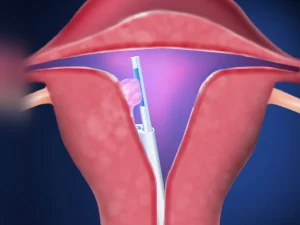

هیستروسکوپی

هیستروسکوپی یک روش جراحی حداقل تهاجمی است، یک لوله نازک و انعطافپذیر بهنام هیستروسکوپ از طریق واژن و ...

اگر شخص قاعدگی منظم داشته باشد، جراح احتمالا اولین هفته بعد از قاعدگی و توقف خونریزی را برای این کار انتخاب میکند. خانمهای یائسه میتوانند در هر زمانی از هیستروسکوپی استفاده کنند و مشکلی برای آنها وجود ندارد.

عمل هیستروسکوپی چقدر طول میکشد؟

عمل هیستروسکوپی چقدر طول میکشد؟ در بیشتر موارد، مدت زمان خود عمل هیستروسکوپی بین ۵ تا ۳۰ دقیقه است؛ اما

هزینه عمل هیستروسکوپی در زاهدان سال 1405چقدر است؟

هزینه عمل هیستروسکوپی یکی از موضوعات مهمی است که افراد درگیر با مشکلات رحمی و پزشکان متخصص به آن توجه